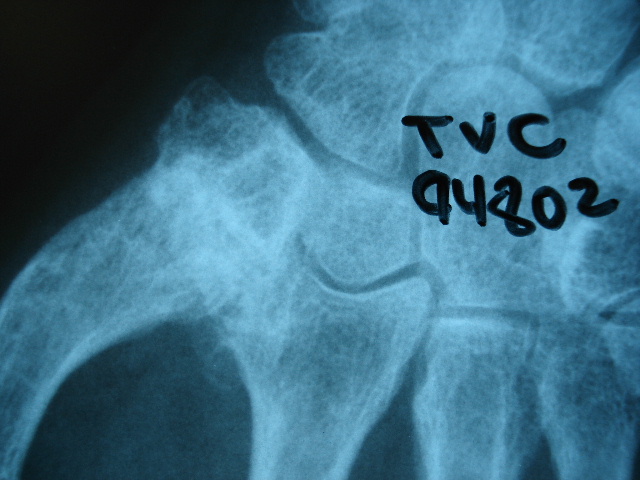

Carpo normal